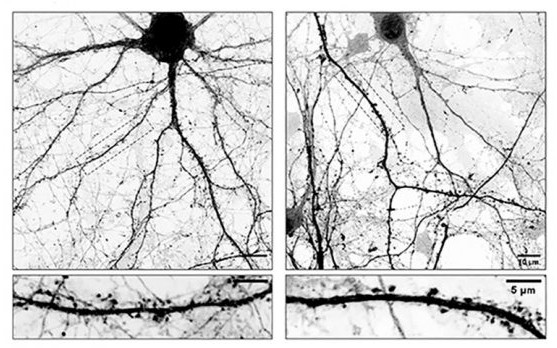

Tal y como destaca Gastón Bisig, investigador del CONICET en el CIQUIBIC y uno de los líderes del estudio, “el problema es que cuando L-Dopa se integra en estos microtúbulos los hace menos dinámicos afectando su ingreso a las espinas dendríticas, estructuras que funcionan como las ‘antenas’ receptoras de la neurona donde se forman las sinapsis”.

“Como consecuencia directa de esto, las neuronas comienzan a perder espinas, claves para la comunicación neuronal. Entendemos que esta inestabilidad sináptica podría explicar algunas de las complicaciones que aparecen luego de un tiempo prolongado de tomar L-Dopa”, señala el experto del CONICET.

Para poder comprobar esta hipótesis, los investigadores utilizaron como modelo de estudio cultivos primarios de neuronas; células nerviosas que se obtienen de una región específica del cerebro de un ratón y que se cultivan en el laboratorio bajo condiciones controladas que les permiten madurar y desarrollarse como lo harían en el cerebro.